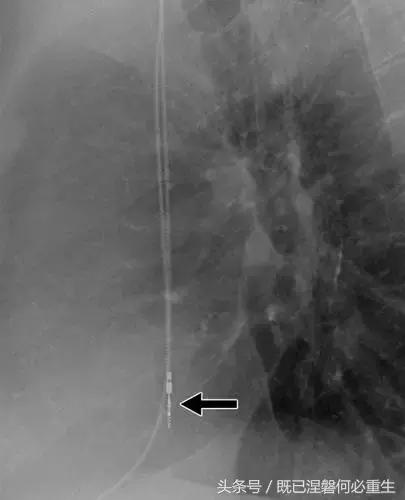

图。 7A 79岁的男性患有电极折断和迁移。

A,初始胸前X线片显示Pacesetter双腔起搏器低于锁骨的心房导线不完全断裂(变薄)(箭头)。